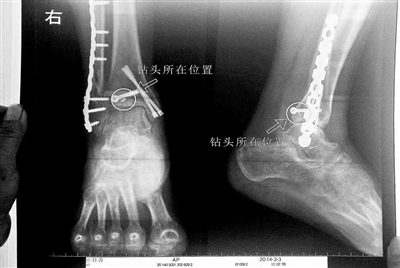

胡女士的腿部X光圖

看著X光片中自己腿內的異物,胡女士就感到莫名的擔憂。胡女士于2013年3月在北京市豐臺區(qū)右安門醫(yī)院進行了一次骨折手術,術后醫(yī)生才發(fā)現手術時用來打眼用的鉆頭不慎遺留在了胡女士的骨頭中,并且無法取出。

近日,在豐臺區(qū)右安門醫(yī)院,北京青年報記者見到了胡女士,她走起路來顯得一瘸一拐,腿腳并不利索。在她帶來的X光片上,可以清晰地看到,有一個異物存在于腿內部。

“我當時就嚇蒙了,怎么會有一個鉆頭在骨頭里?”胡女士余悸未消地說,第二天拍攝的X光片顯示,2厘米左右的鉆頭遺留在她右腳腳踝上部的骨頭內。

胡女士說,當時旁邊的醫(yī)生勸慰自己,稱鉆頭留在腿里并不會有什么問題。出院后,胡女士每個月都會來醫(yī)院做復查,拍X光片。她說,每次都能夠清晰地看見自己骨頭里的那個明晃晃的“小東西”。